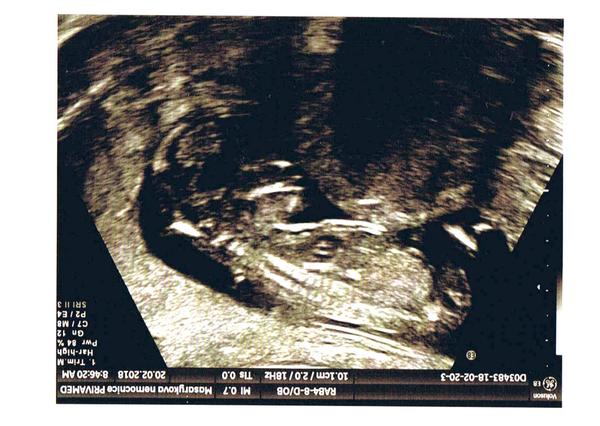

@lenka_1981 Ahoj, ve 13tt lze poznat jen podle sklonu pohl. výběžku, takže je třeba mít fotku z profilu, z této to bohužel poznat nepůjde..

@linee byla jsem minuly tyden 21+0 tt a doktor me vytocil...rikal,ze je to na ueceni jeste brzy a musim.si pockat 😡 mel blbou naladu a plnou cekarnu pupkatych mamin co cekaly na ultrazvuk...objednala jsem.se do Plzne na genetiku a 3D ultrazvuk...takte 13.12.uz snad budu vedet a pisnu jestli holka nebo kluk 😉